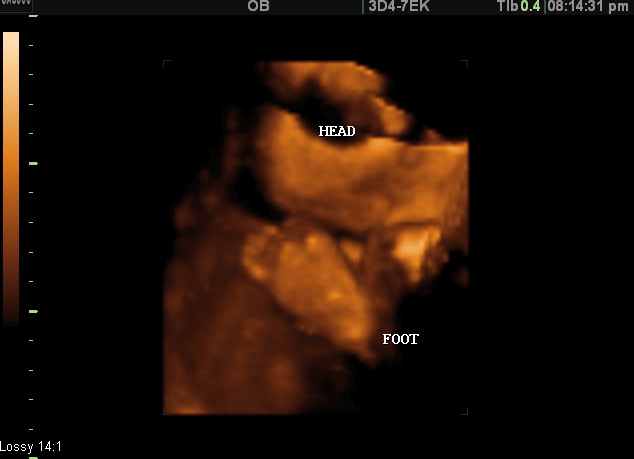

Image Gallery 4d Ultrasound Sarasota Florida 3d Ultrasound